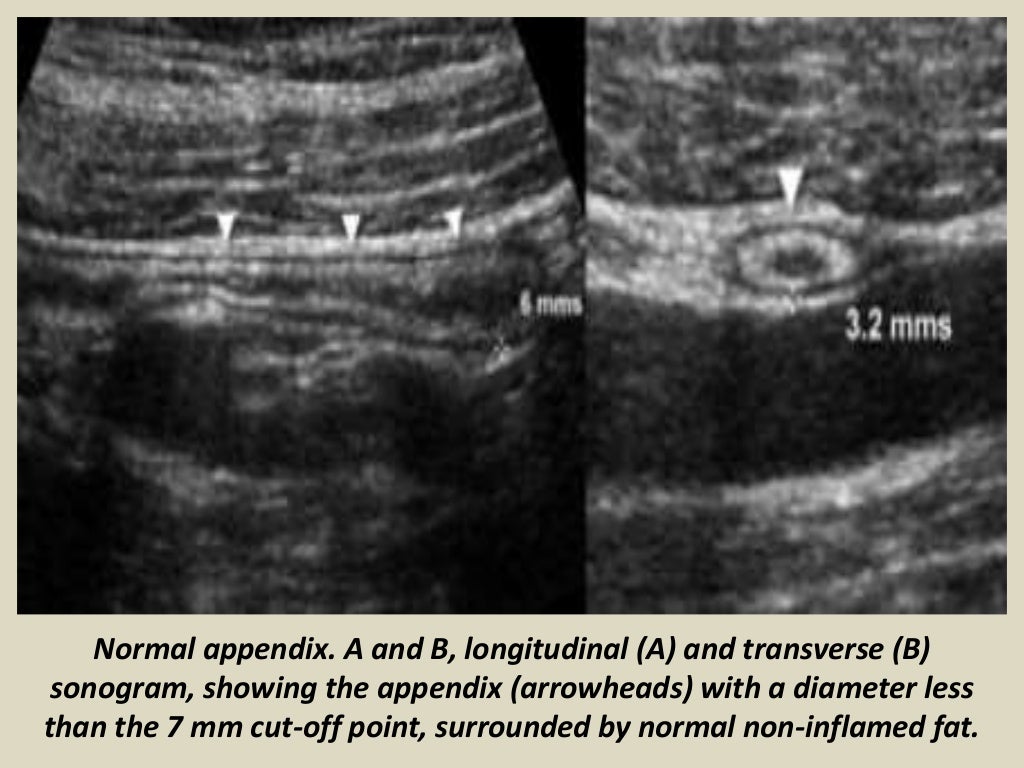

The normal fatty meso-appendix can be identified if outlined by some intraperitoneal fluid as in this patient, and is moderately hyperechoic, soft and well-compressible. Roughly 4-6 hours after the onset of symptoms, the inflammation begins to affect the meso-appendix, which becomes larger, more hyperechoic and non-compressible (arrowheads).

In addition, a MMT < 3 mm should be regarded as normal in children less than 6 years old. Wiersma et al [ 10] also reported that the sizes of the MOD and the MMT in a normal appendix in children was 0.21-0.64 cm and 0.11-0.27 cm, respectively. Go to:

The normal diameter of the appendix can be as high as 12.8 mm. 91.5% of normal appendices are larger than 6 mm in our study. The normal wall thickness is larger than 3 mm in 8% of normal appendixes. Hence, relying on appendix size alone may lead to misdiagnosis and mismanagement.

Appendicitis should not be diagnosed by size alone. Normal appendices can measure 13 mm in width and 35 cms in length, so it is important to consider the ancillary findings of obstruction, ischemia, inflammation and perforation.. However, the identification of a normal appendix is less consistent, and in many instances, appendicitis cannot.

The normal caliber of a collapsed appendix on computed tomography (CT) is generally accepted as ≤ 6 mm and can be identified in 43-100% of patients depending on factors such as contrast enhancement and slice thickness (Figs. 3a, b) [].However, if distended by air or contrast material, a normal appendix can measure up to 10 mm.

Among these patients, the mean diameter of the normal appendix was 5.6-5.7 mm, with a normal range (95% CI) encompassing 2.7-8.7 mm and 34-39% of normal appendixes measuring greater than 6 mm in diameter. Although this represents a much larger sample than prior studies, the mean normal appendiceal diameter is concordant with diameters.

Appendicitis should not be diagnosed by size alone. Normal appendices can measure 13 mm in width and 35 cms in length, so it is important to consider the ancillary findings of obstruction, ischaemia, inflammation and perforation.. However, the identification of a normal appendix is less consistent, and in many instances, appendicitis cannot.

The normal diameter of the appendix can be as high as 12.8 mm. 91.5% of normal appendices are larger than 6 mm in our study. The normal wall thickness is larger than 3 mm in 8% of normal appendixes. Hence, relying on appendix size alone may lead to misdiagnosis and mismanagement.